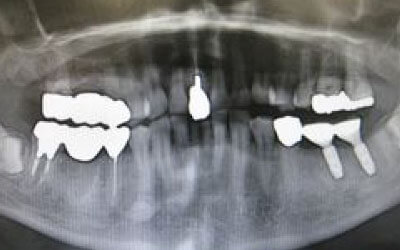

私たちが噛むとき、歯には何十キロもの力がかかっています。そのため、歯の本数が減るほど、残った歯にかかる負担は大きくなります。ブリッジ治療の場合も、失った歯にかかっていた力を前後の健康な歯が支えることになります。その結果、残っている歯には、抜歯前よりも1.5倍から2倍ほど強い力がかかるのです。

入れ歯を使うと、バネをかけている歯や他の残っている歯に大きな負担がかかります。多くの人は無意識のうちに残った歯で噛んでしまうため、その歯が過度に使われて力がかかりすぎ、結果として歯が折れるなど、歯の寿命を縮めてしまいます。一方、インプラントは人工の歯根が直接骨に力を伝えるため、残っている歯への負担が格段に少なくなります。

ブリッジなどの治療では、支えとなる前後の歯を大きく削らなければなりません。場合によっては、虫歯でなくても歯の神経を抜くことがあり、神経を抜いて被せ物をすると、その歯は急速に寿命が短くなってしまいます。一方でインプラント治療は、前後の歯を削ったり神経を取ったりする必要がありません。健康な歯をできるだけ残すことは、歯の寿命を延ばすために非常に重要です。